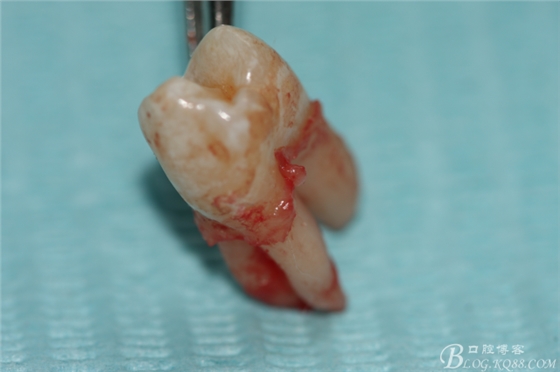

5.上頜離體第一前磨牙牙根形態(tài)